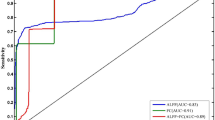

To investigate the brain functional abnormality of hyperthyroid patients before and after treatment for one month using resting-state functional magnetic resonance imaging (rs-fMRI). Amplitude of low-frequency fluctuation (ALFF) and seed-based functional connectivity (FC) analysis were performed in 27 new-onset untreated hyperthyroid patients relative to 30 healthy controls. In addition, follow-up data were available for 19 patients treated with methimazole for one month. Compared with healthy controls, patients exhibited lower ALFF in the right posterior cingulate cortex (PCC); increased FC in the bilateral anterior insula (AI), bilateral posterior insula (PI) and left anterior lobe of the cerebellum (ALC); and decreased FC in the bilateral lateral prefrontal cortex (LPFC), the right medial temporal gyrus (MTG) and the bilateral PCC. Compared with the hyperthyroid status, patients with improved thyroid function showed increased FC in the right LPFC and right dorsolateral prefrontal cortex (DLPFC). Subsequently, Pearson’s correlation analyses were performed between abnormal ALFF, FC, neuropsychological assessment and serum free triiodothyronine (FT3) levels. The results indicated that the alterations in regional and network-level brain functions, which might underlie different psychiatric complications were dynamic and interactional processes in hyperthyroidism. Moreover, the improvement in regional brain FC was correlated with the efficacy of anti-thyroid medication.

In the present study, we applied resting-state fMRI to investigate the abnormalities of brain function in patients with hyperthyroidism before and after the intake of methimazole over a one-month period. More specifically, to measure differences in regional cerebral activity, the amplitude of low-frequency fluctuation (ALFF) approach was used to detect alterations of regional brain function in hyperthyroid patients compared with healthy controls. ALFF is thus a measure reflecting the spontaneous neural function of local brain regions16. ALFF analysis has been widely used to study baseline activity and to uncover the latent mechanism of neurodegenerative disease, such as Parkinson’s disease17 and schizophrenia18. To explore the aberrant covariation of the time-course activity across regional brains, the peak points of brain regions identified by ALFF analysis were used as seeds for whole brain FC analyses19. Compared with traditional seeding approaches to select particular brain regions with the prior hypothesis, this method of locating seeds could provide an unbiased study of abnormalities in full-brain function. Monitoring resting-state brain function might provide exhaustive information about regional activity and network-level cerebral function abnormalities pre-therapy and about regional and network changes with improved thyroid function. Based on the combination of ALFF and FC analyses, we sought to further investigate the mechanisms underlying emotional and cognitive impairments and their possible reversibility after anti-thyroid therapy over one month.

FC analysis

Before treatment, the bilateral anterior insula(AI), posterior insula(PI) and left anterior lobe of the cerebellum(ALC) showed significantly stronger FC to the right PCC in the hyperthyroid group than the control group (p < 0.001, AlphaSim-corrected or small volume-corrected) (Table 2, Figs 2 and 3). However, the bilateral LPFC, right medial temporal gyrus (MTG) and bilateral PCC showed significantly weaker FC from the right PCC in the hyperthyroid group than in healthy controls (p < 0.001, AlphaSim-corrected or small volume-corrected) (Table 2, Fig. 2). One month after treatment, significantly increased strength of FC between the right PCC and right LPFC and right DLPFC was found in the 19 hyperthyroid patients (p < 0.001, AlphaSim-corrected or small volume-corrected) (Table 2, Fig. 3).

Differences in whole-brain FC between hyperthyroid patients and healthy controls before anti-thyroid therapy (p < 0.001, AlphaSim-corrected or small volume-corrected). The red color indicates increased FC, and the blue color means the decreased FC in the hyperthyroid group compared with the control group.

This investigation demonstrated brain function improvement in patients with hyperthyroidism after short-term treatment. We found the alterations of regional and network-level brain function in patients with hyperthyroidism. It should be noted that there was increased FC from the right PCC to the bilateral insula before treatment, and there was a negative correlation between the increase in the strength of FC from the right PCC to the right LPFC and the decrease in FT3 after anti-thyroid therapy. These findings suggest that the changes in regional and network-level brain function identified by rs-fMRI might be dynamic, and an interactive process underlies the neuropsychiatric manifestations of hyperthyroidism. Additionally, the change in FC was associated with therapeutic efficacy. This finding might suggest that these brain functional networks are correlated with the pathogenesis and progression of hyperthyroidism.

Our results indicated that the dysfunction in regional FC after anti-thyroid treatment could be improved, and the improvement in FC was negatively correlated with the disease severity. A previous PET study demonstrated that treatment with methimazole induced a significant cluster of increased metabolic activity only in the right superior frontal cortex compared with the hyperthyroid status11. Another follow-up study with 1H-MRS also showed that the Cho/Cr ratios in the right prefrontal cortex were higher than pre-therapy29. In the current study, we speculated that the right frontal cortex may be a pivotal juncture in the restoration of brain function in patients with hyperthyroidism. In terms of the results of the correlation analysis, On the one hand, the positive correlation between the he decrease in FT3 and the duration of disease, which might suggest that when hyperthyroidism is more severe, the sensitivity to methimazole treatment is better. On the other hand, the recovery of the strength in FC from the right PCC to right LPFC was negatively correlated with the decrease in FT3, integrating the positive correlation between the decrease in FT3 and the duration of hyperthyroidism. This result might mean that when the severity of hyperthyroidism is more severe, the recovery of brain function occurs more slowly. Additionally, considering that a change in the DLPFC could not be found before anti-thyroid therapy, the reliability of this result should be further investigated.

ALFF and FC map analyses were performed with SPM8 software (http://www.fil.ion.ucl.ac.uk/spm/). To characterize the pretherapeutic differences in ALFF and FC in the 27 hyperthyroid patients compared with the 30 normal subjects, a two-sample t-test was performed voxel-by-voxel after controlling for several covariates, including age, sex, mean value of head motion and years of education. Then, a paired-samples t-test was used to assess the possible changes in ALFF and FC after the administration of methimazole for one month in the group of 19 patients. Head motion was used as a covariate. For all of the above analyses, significance in the resulting statistical maps was set at 0.001, and a gray matter (GM) group mask was involved in the ALFF and FC calculations. The correction of results for multiple comparisons was divided into two parts: initially, to precisely define the peak points of brain regions with abnormal local brain activity in hyperthyroid patients as the seed regions for further FC analysis. The result maps of ALFF were corrected with the AlphaSim program (individual voxel p-value = 0.001, GM group mask, iteration = 1000) in DPABI software. The statistical threshold for pre-therapy ALFF was set at p = 0.001 and cluster size >35 voxels. Subsequently, the primary results of FC were displayed as statistical parametric maps (SPMs) in a standard MNI space at an initial threshold probability of p = 0.001 (uncorrected for multiple comparisons) and a cluster size threshold of 15 contiguous voxels. To fully explore the possible changes in brain connectivity before and after anti-thyroid therapy, statistical inference was performed in two steps with regard to the results of whole-brain FC calculations. First, a relatively strict statistical threshold of p = 0.001 in AlphaSim corrected for multiple comparisons was applied to the whole brain. The statistical threshold for FC was set at p = 0.001 and cluster size >68 voxels in pre-therapy and cluster size >44 voxels in post-treatment. Second, based on the results reported in previous studies10,11,12,13,14,15, 29 for the posterior cingulate cortex, frontal cortex, anterior cingulate cortex, temporal gyrus, cerebellum, insula and hippocampus, we used small volume-corrected (SVC) over these brain regions predicted a priori to demonstrate abnormalities in hyperthyroidism. These flexible statistical analyses were conducted using a family-wise error(FWE)-corrected threshold of p < 0.05 over the volume of the SVC-based hypothetical region, with a cluster size threshold of 15 contiguous voxels. Compared with a stricter correction for the whole brain, the SVC method enables hypothesis-driven analyses to be conducted with correction for multiple comparisons particularly in the cerebral region of interest43, 44.